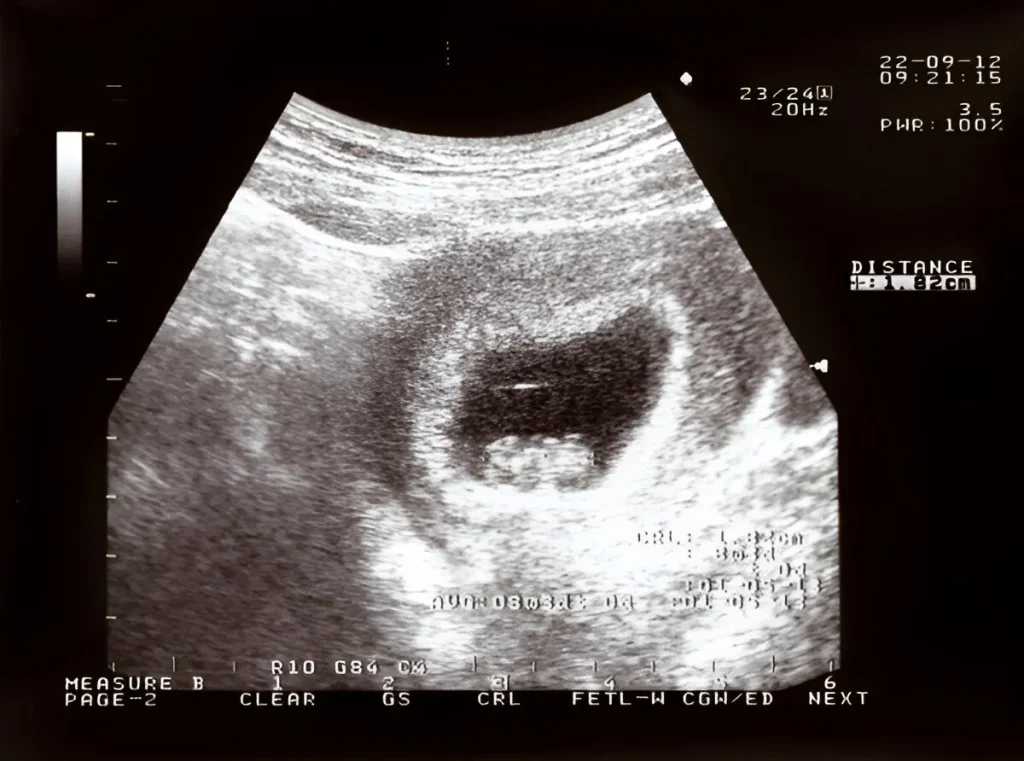

obstetrics-(OBS)-doppler-in-kharghar-advanced-diagnostic-centre-best-diagnostic-centre-henotic-diagnostics-kharghar-navi-mumbai